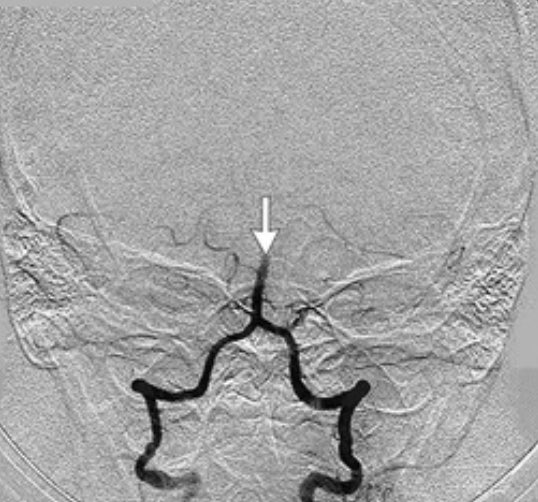

Oren Gottfried, MD on Twitter "43 year old woman with impaired Binocular Vertigo Binocular vision dysfunction is usually a sign that something’s affecting how well your eyes work with each other and your brain. Bppv (benign paroxysmal positional vertigo) psychogenic dizziness / chronic subjective dizziness. Binocular vision dysfunction (bvd) occurs when your eyes don’t line up, causing problems communicating with your brain. But when the eyes do not work smoothly together and are. Binocular Vertigo.